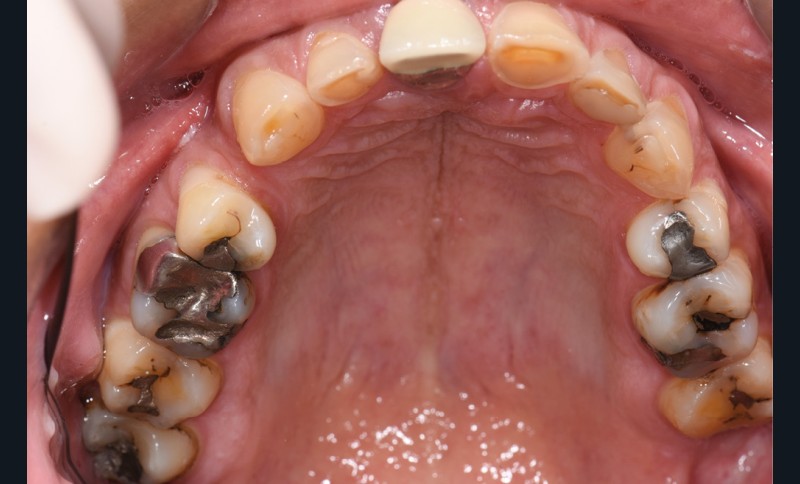

L’étiologie de cette usure est multifactorielle, revêtant une composante de type attrition (usure par contact dento-

dentaire), une composante abrasive avec un brossage traumatique et, en dernier lieu, une légère composante tribo-érosive de par une pratique importante de sport avec gel et boisson acide (fig. 1-4) [1].